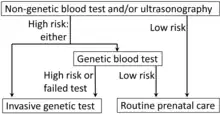

The goal of prenatal genetic testing is to identify pregnancies at high risk of abnormalities, allowing for early intervention, termination or appropriate management and preparation measures.[25] Prenatal genetic testing is done by means of different screens and diagnostic tests. A screen informs an individual of the potential for certain abnormalities occurring, whereas, the diagnostic testing is used to confirm/diagnose specific abnormalities exist within the fetus. Prenatal screens are typically less invasive than prenatal diagnostic tests. They come with much lower risk, however, the results are not as definitive as diagnostic tests. Providers often recommend following up with a diagnostic test upon receipt of a positive result from a specific screen.

Non-invasive techniques include examinations of the woman's womb through ultrasonography and maternal serum screens (i.e. Alpha-fetoprotein). Blood tests for select trisomies (Down syndrome in the United States, Down and Edwards syndromes in China) based on detecting cell-free placental DNA present in maternal blood, also known as non-invasive prenatal testing (NIPT), have become available.[35] If an elevated risk of chromosomal or genetic abnormality is indicated by a non-invasive screening test, a more invasive technique may be employed to gather more information.[36] In the case of neural tube defects, a detailed ultrasound can non-invasively provide a definitive diagnosis.

Testing guidelines and qualifying risk factors for invasive testing

The American College of Obstetricians and Gynecologists (ACOG) guidelines currently recommend that anyone who is pregnant, regardless of age, should discuss and be offered non-invasive prenatal genetic screening and diagnostic testing options.[58] Non-invasive prenatal genetic screening is typically performed at the end of the 1st trimester (11–14 weeks) or during the beginning of the second trimester (15–20 weeks). This involves the pregnant woman receiving a blood draw with a needle and a syringe and an ultrasound of the fetus. Screening tests can then include serum analyte screening or cell-free fetal DNA, and nuchal translucency ultrasound [NT], respectively.[59] It is important to note that screening tests are not diagnostic, and concerning screening results should be followed up with invasive diagnostic testing for a confirmed diagnosis. Invasive diagnostic prenatal genetic testing can involve chronic villus sampling (CVS) or amniocentesis.[60] The ACOG recommends genetic screening before pregnancy to all pregnant women planning to have a family.[61] After comprehensive counseling and discussion that acknowledges residual risks, it is important to respect the patients' right of choosing whether or not to pursue any component of genetic testing.